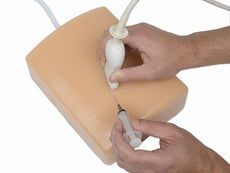

Gain proficiency in performing transvaginal ultrasound exams with our CAE Blue Phantom female pelvis models. The patented Simulex internal tissue allows learners to develop, practice and verify ultrasound imaging skills, including using ultrasound system controls, positioning and moving the transducer, recognizing internal pelvic anatomy and pathology and using gynecological ultrasound calculation packages to measure cysts, masses, and other structures. These models are excellent for 2D, 3D, and 4D ultrasonography imaging techniques. Choose from three options: General Pathology, Intrauterine & Ectopic Pregnancy, or Sonohysterographay & Sonosalpingography.